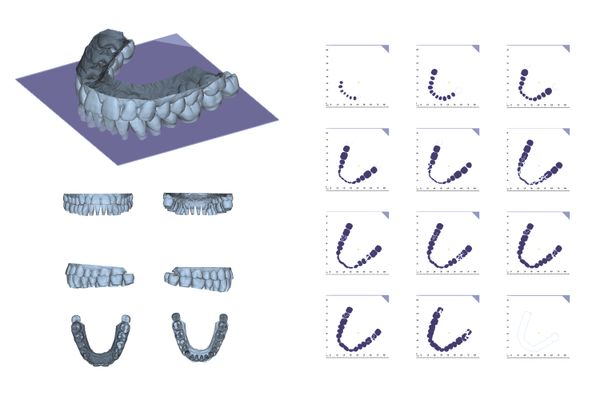

The entire project consists of a variety of materials, including secondary processed archival images, fashion magazine images of blister packs and affixed brackets, digitally processed archives of perfect occlusal curves, and conceptualized images that interact with simple devices. Starting from early and recent images of cosmetic dentistry, the project attempts to appropriated and secondary creations to visualize the invisible power of cosmetic dentistry, and ultimately leads to an established future where the incorruptible orthodontic bracket becomes a brand new organ of the human being.